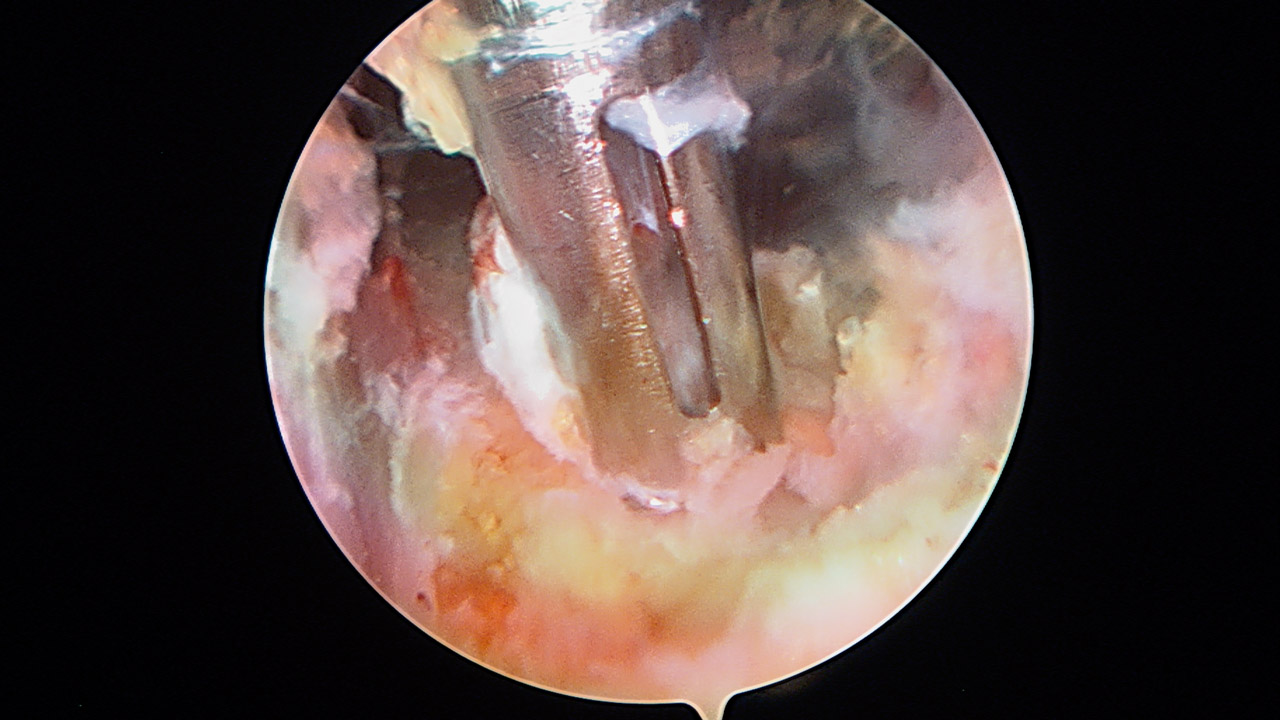

Presentamos una técnica quirúrgica artroscópica para los casos de inestabilidad traumática o atraumática de hombro, con hiperlaxitud multidireccional asociada, en los que hayan fracasado los tratamientos conservadores u otras técnicas quirúrgicas de plicatura capsular, y no presenten déficit óseo importante. Consiste en la plicatura del ligamento glenohumeral inferior (anteroinferior y posteroinferior) y la realización de una ligamentoplastia de refuerzo anterior artroscópica con aloinjerto en disposición transubescapular.

We present an arthroscopic surgical technique for cases of traumatic instability or atraumatic of the shoulder, with associated multidirectional hyperlaxity in which conservative treatments have failed, or other surgical techniques of plication capsular, and do not present major bone deficits. It consists of the plication of the lower glenohumeral ligament (anteroinferior and posteroinferior) and the accomplishment of an arthroscopic anterior reinforcement ligamentoplasty with allograft in a trans-scapular arrangement.